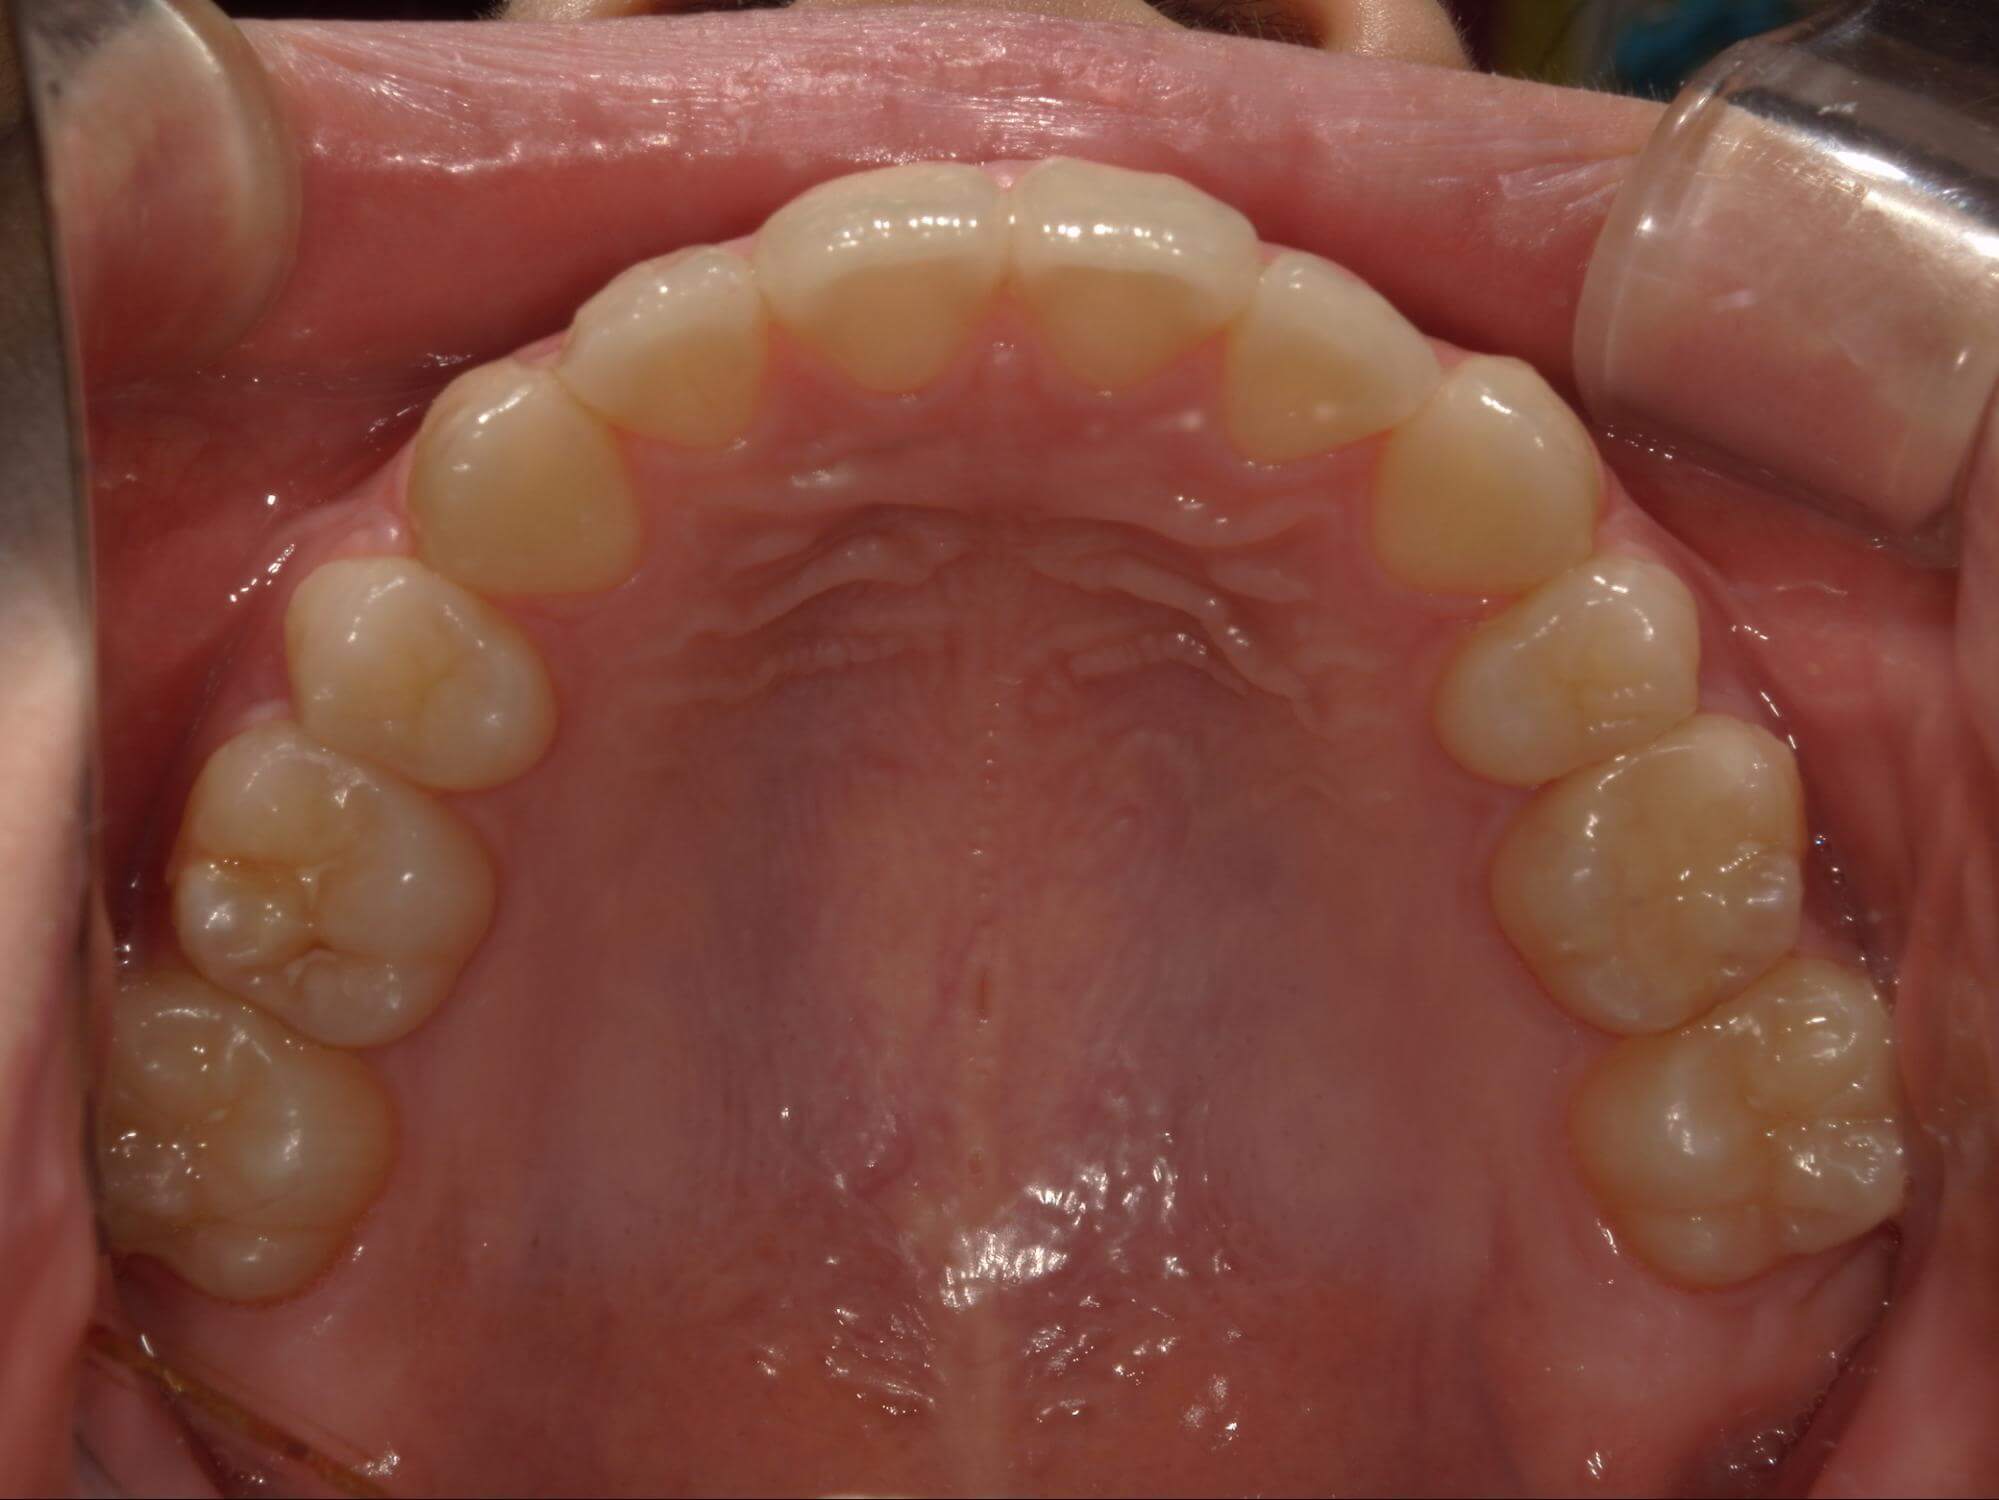

| 年齢・性別 | – |

|---|---|

| 主訴 | 叢生が気になる |

| 治療期間・回数 | 2年 |

| 費用 | 935,000円 |